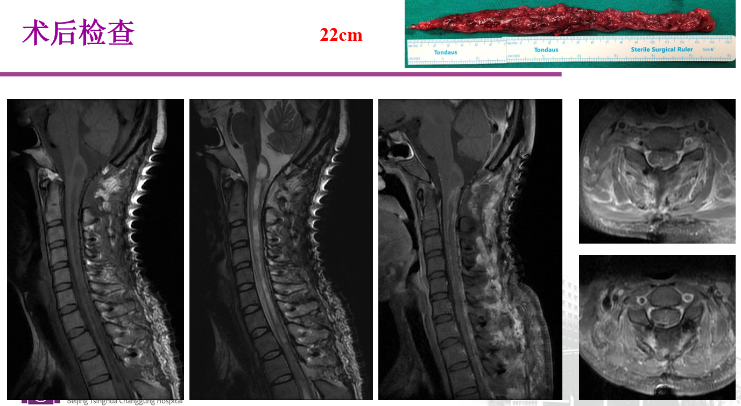

图3 王贵怀教授—巨大脊髓室管膜瘤切除术(22cm)